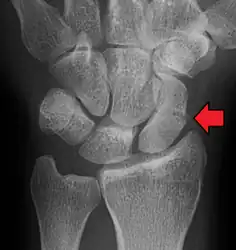

A more obvious scaphoid fracture on a scaphoid view X ray

Fracture of the tubercle of the scaphoid bone of the wrist